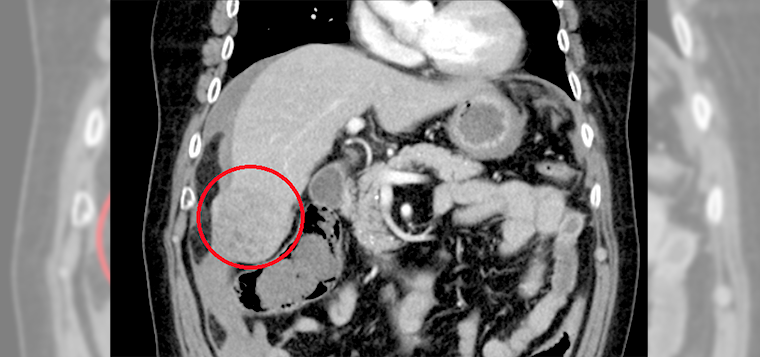

▲電腦斷層檢查發現患者肝臟有1處5公分大腫瘤。(圖/台北慈濟醫院提供)

【NOW健康 陳如頤/新北報導】70歲的林爺爺,突如其來的劇烈腹痛,竟是肝腫瘤!來到台北慈濟醫院,電腦斷層檢查顯示1顆5公分大的肝腫瘤,情況危急。經診斷為早期肝癌,且未轉移,由一般外科陳昱天醫師進行手術。由於林爺爺與太太相依為命,沒有工作,考量經濟壓力,起先婉拒所有治療方案,所幸在醫師、專師、護理師及社工師不懈協調下,最終由陳昱天醫師執行手術,將腫瘤及周邊組織切除,術後林爺爺恢復狀況良好,5天後平安出院。